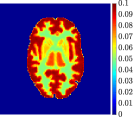

Figure 4, Figure 5, and Figure 6 show the mean images computed over the ten reconstructions obtained by the methods reg-AS-TR, reg-GN, and by the Matlab routine lsqcurvefit implementing a standard Trust-Region-Reflective least-squares algorithm [11, 10]. We used the noise-free IF and the perturbed IF with and of noise, respectively. Figure 7 contains mean and standard deviation values of the kinetic parameters computed over the ten reconstructions and over each one of the four homogeneous regions, for each one of the three noise levels on the IF.

Finally, Figure 8 represents the last frame of the dynamic PET data reconstructed with the mean parametric values returned by reg-AS-TR, reg-GN, and lsqcurvefit, with respect to the noise-free, 10-noise, and 20-noise IFs.

In general, reg-AS-TR and lsqcurvefit seem to provide similar mean reconstructions, although uncertainties associated to lsqcurvefit are significantly bigger. On the other hand reg-GN seems to systematically underestimate the parameter values within region . Furthermore and as expected, for all methods the quality of the parametric reconstructions deteriorates with increasing noise levels; this is more clear from the and parametric images, probably due to the different sensitivities of the data with respect to the model parameters [37]. In reg-GN and lsqcurvefit some artifacts can be observed at the edges of the homogeneous regions, especially around region and region , whereas the effect of regularization in reg-AS-TR results in a reduced presence of artifacts while the structure of the regions is preserved. This general trend is confirmed by the error-bar plots of Figure 7. Finally, the frames in Figure 8 corresponding to reg-AS-TR show a significant improvement of the image quality with respect to what is provided by the other two approaches.